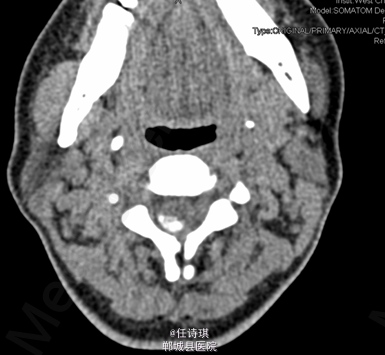

女,46岁8月,因“颈部不适3年,右上肢软弱疼痛伴双下肢胀痛1年”入院。3年前无明显诱因出现颈部不适,以局部胀痛为主,劳累后加重休息后可缓解,不伴上肢放射痛。遂未予特殊处理。1年前出现右上肢酸麻肿痛,以肘关节疼痛和手部皮肤麻木为主,行走约10分钟后自觉双小腿后侧胀痛,休息后可缓解。在当地医院诊断为“网球肘、颈椎病”予以对症治疗,但上述症状无明显改善。行MRI、CT等检查,诊断为“C2椎管内肿瘤”,未予特殊治疗。为求进一步诊断今日由门诊以“C2椎管内占位,性质?”收入院

专科查体:视:脊柱无明显畸形。触:颈胸部各棘突无明显压、叩痛。四肢肌张力正常,右手皮肤触觉减退。动量:右侧上肢肌力IV级,左侧肢体V级。右侧上肢腱反射活跃,双侧膝腱反射活跃,跟腱反射正常引出。Hoffman征阳性,Babinski征未引出。外院MRI示:C2椎管内脊髓背侧占位病变,脊膜瘤可能。T2椎体内异常信号,多为血管瘤。。

初步诊断:1、颈2节段椎管内占位伴不全四肢瘫(Frankel D):脊膜瘤?黄韧带骨化? 2、胸2椎血管瘤 处理:全麻下行经后路颈2全椎板切除、椎管探查减压、椎管内占位切除活检术,